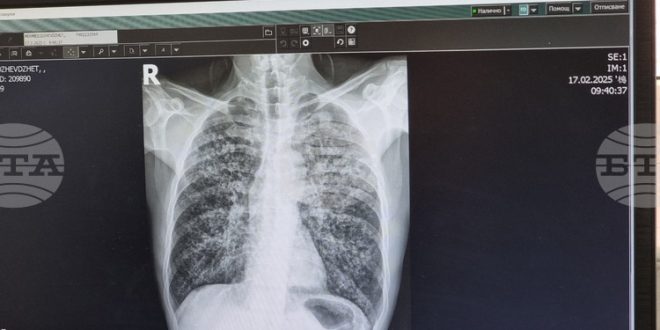

Плевенската университетска болница „Д-р Георги Странски“ стартира инициатива за оценка на риска от белодробна туберкулоза, съобщи Българската Телеграфна агенция (БТА). Кампанията ще се проведе в периода от 8 до 12 декември в отделението за диспансерно наблюдение на пациенти с пневмо-фтизиатрични заболявания. Прегледите ще се извършват ежедневно от 12:30 до 14:30 часа.

За да бъде гарантирана ефективността на кампанията, болницата изисква предварително записване, което може да бъде направено на място или чрез телефонен контакт на номер 064/802 994. Всички процедури, свързани с кампанията, ще бъдат напълно безплатни за участниците, независимо дали имат здравна осигуровка. Прегледите включват попълване на анкети, медицински консултации и, ако е необходимо, допълнителни изследвания.